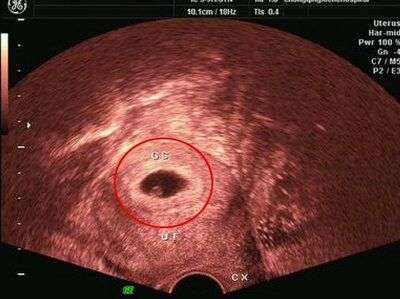

孕囊其实只有在怀孕早期可以看得见,当孕妈咪还不知道自己已经怀孕,只知道该来的月经还没来的时候,如果一旦确定怀孕,那么就要从上次停止月经的时间计算预产期。而从上次停止月经的时间计算,向后数35天,那么孕囊基本上就能在B超里显示出来了。而这时已经是怀孕第五周了,这个时候孕囊的直径大小约为2cm。

随着胎儿的不断增长,孕囊也会不断的扩大的,到了孕8周,也就是怀孕60天左右的时间时,孕囊的直径可以增加到5cm。此时观察到的孕囊,其位于子宫的宫底、前壁、后壁、上部、中部等位置,清晰可见,而且呈规则的椭圆形或者圆形。但是也有一种可能,孕囊位于子宫的下部,而且形状不规则,且通过B超发现有些模糊,而此时孕妇主诉有腹痛或者见红的现象,那么这位孕妇很有可能要流产了。(揭秘羊水指数标准!教您如何进行测量羊水量?)

怀孕6周,胎儿的身长大概在0.85cm;怀孕7周,胎儿的身长大概在1.33cm;怀孕8周,胎儿的身长大概在1.66cm。这个时候胎儿已经基本上成型了,四肢及头部、躯干部位都已经可以通过B超清晰的看出来。这个时候胎囊也已经不小了,占到了官腔的一半左右。

细心的孕妈咪可能会发现,在孕早期的B超单上,都会显示孕囊的大小,尺寸大小直要比宝宝的体长大出一倍左右,基本上是没有问题的。